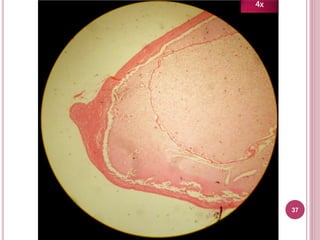

37

4x

Características

 Cápsula prolígera con

protoescólex dentro

 3 capas (de externo a

interno):

1. Fibrosa o adventicia

2. Laminar o hialina

3. Germinal

 NO compartimentalizada

 Produce hidatidosis

unilocular Tejido

hepático

Capa fibrosa o

adventicia

Capa laminar o

hialina

Capa

germinal

Protoescólex

Quiste hijo

1. Fibrosa o adventicia; 2. Laminar o hialina; 3. Germinal